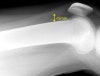

- Very Small

There appears to be a small amount of fluid in the supra-patella pouch (left arrow).

There is also fluid in Hoffa's Triangle (right arrow).